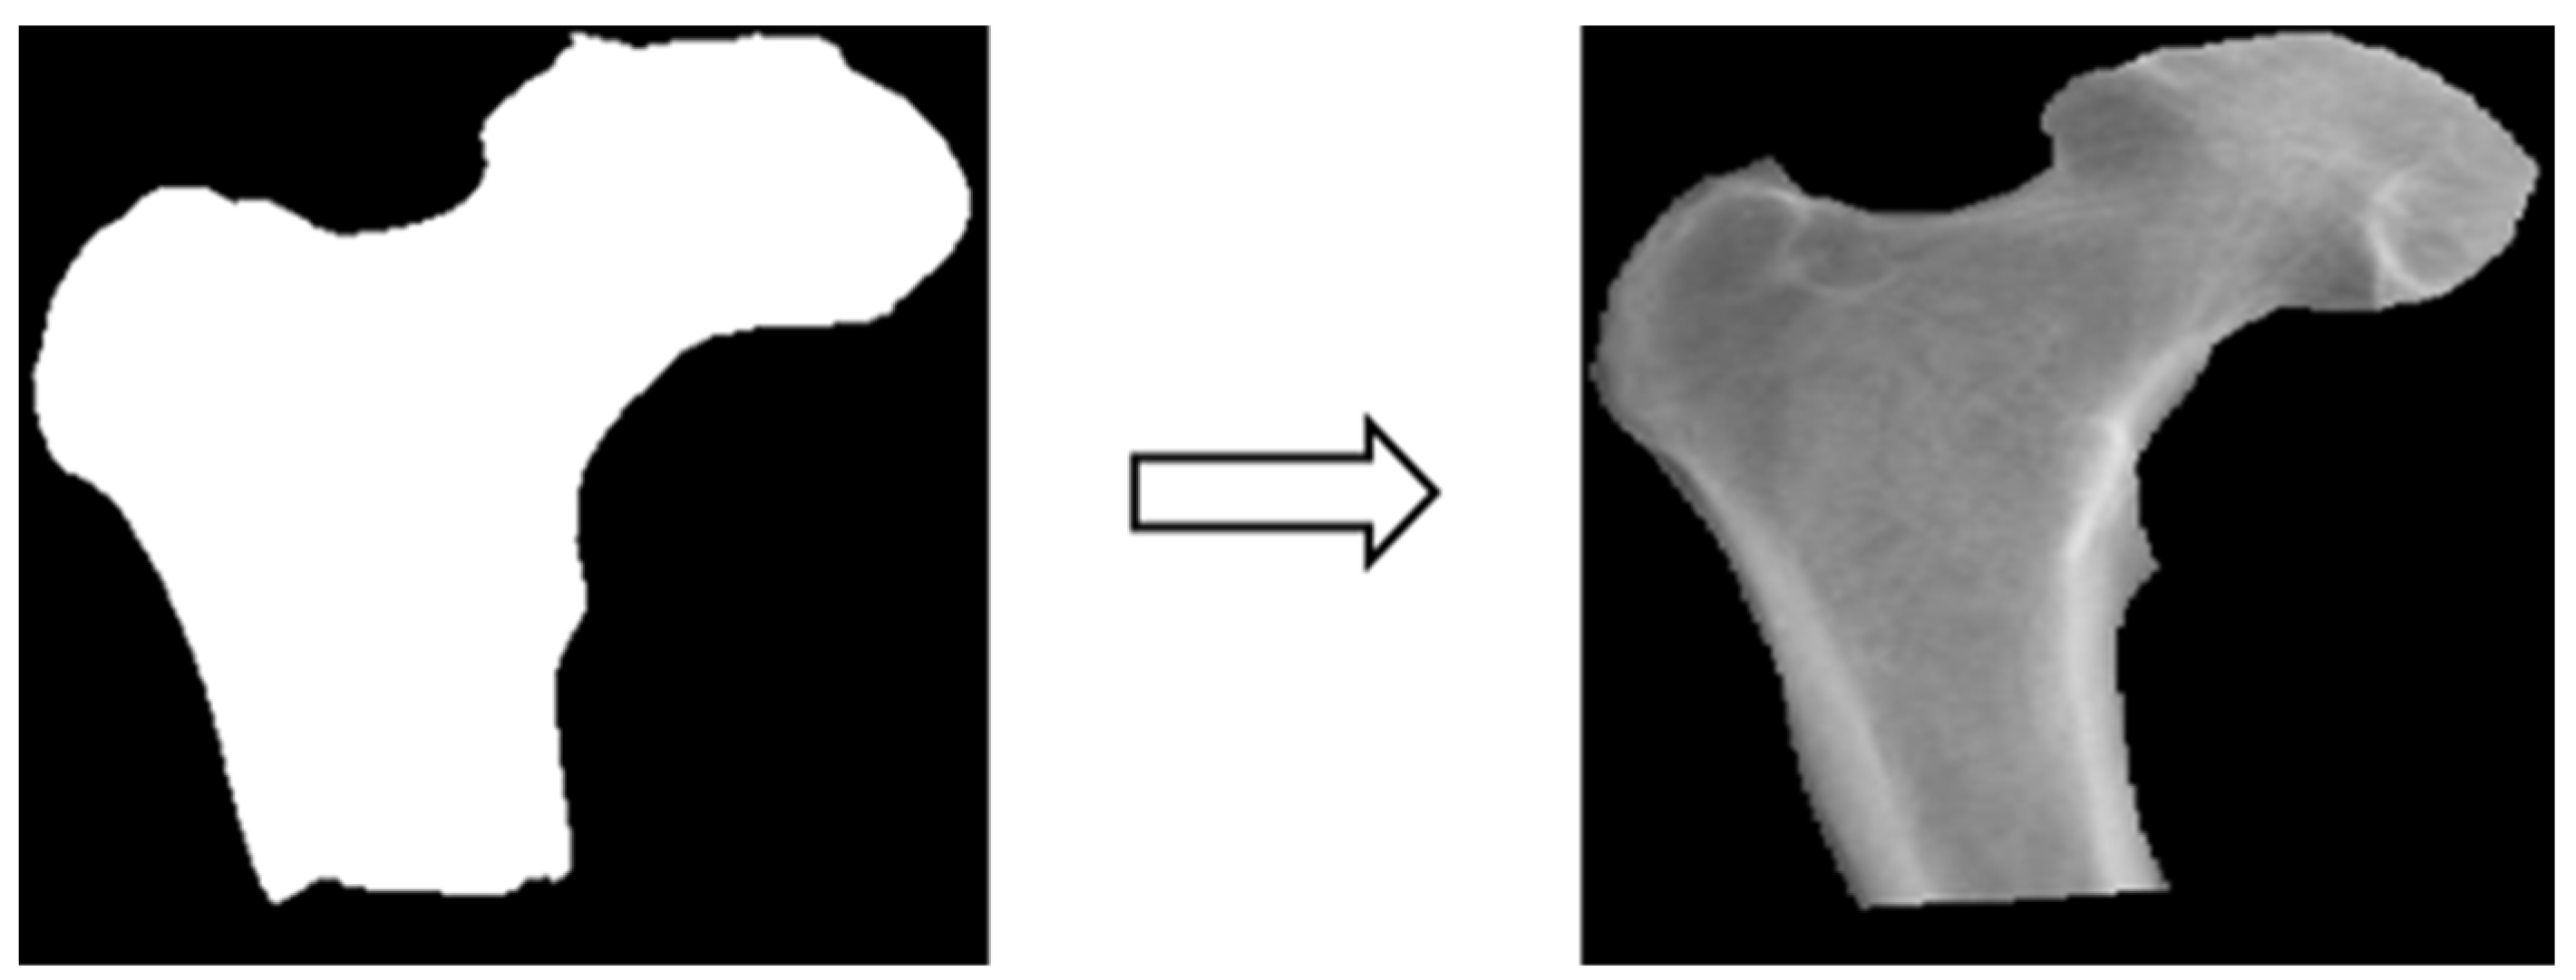

3.3.3. Image Matting

Based on the four parts of the image segmentation of the binary image and the original X-ray image together, the original X-ray image only retains the part of the image segmentation as shown in Figure 4; the other non-part of the contour of the background is removed, and the image is de-behind in the hope that it can enhance the accuracy of the classification of the depth of the learning process, and then the image classification will be segmented images and not segmented images will be compared.

Figure 4.

Image matting.